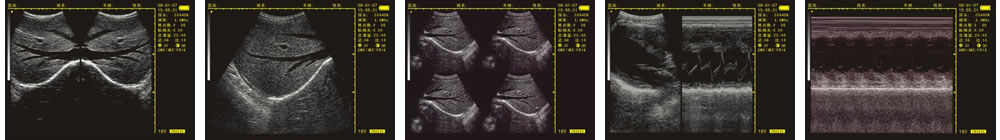

優(yōu)質(zhì)的成像效果

V-20掌上B型超聲診斷儀(動物版)一流的數(shù)字成像技術(shù),圖像更清晰